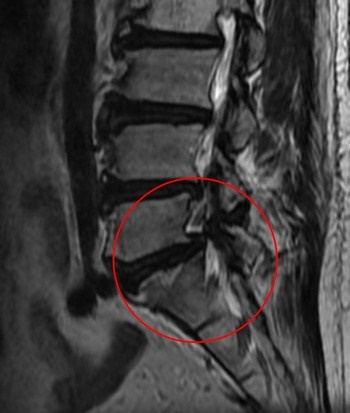

影像檢查顯示,張先生的第五節腰椎椎弓骨折合併脊椎解離。洪祥益主任表示,這類病人多半表現為腰痠背痛、久坐久站困難,通常可先藥物治療觀察,但相較於其他類似問題的病人,張先生疼痛異常明顯,手術中發現脊椎關節內長滿痛風石,這些痛風石如白色黏稠物般,附著在神經與關節縫隙間,若不清乾淨,就會持續引發神經發炎與疼痛,甚至比坐骨神經痛更強烈。團隊透過顯微鏡,在不傷及神經的情況下,仔細將痛風石刮除清理,再以微創固定融合手術完成治療。

左圖:影像檢查顯示,張先生的第五節腰椎椎弓骨折合併脊椎解離。